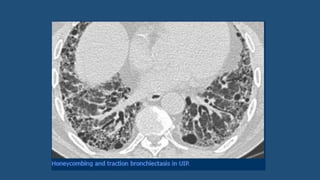

Honeycombing

• Presence of small cystic spaces with irregularly thickened walls

composed of fibrous tissue.

• Honeycomb cysts often predominate in the peripheral and sub-

pleural lung regions regardless of their cause.

• Irreversible – no t/t required

• UIP pattern on HRCT is characterized by:

 Subpleural and basal predominance

 Reticulation (with traction bronchiectasis)

 Honeycombing